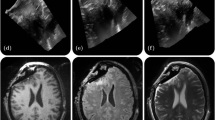

Case 11

The patient was a female in her 50 s diagnosed with a craniopharyngioma. For optic chiasm visualization, the preoperative contrast-enhanced bSSFP score was 2 (Fig. 4A), and the T2WI score was also 2 (Fig. 4B). Tumor resection was performed using the ETSS approach. iMRI revealed significant intracranial air (Fig. 4C, D). The intraoperative contrast-enhanced bSSFP score was 0 (Fig. 4D), and the intraoperative T2WI score was likewise 0 (Fig. 4E).

(A) Optic chiasm visualization with preoperative contrast-enhanced bSSFP scored 2. (B) Optic chiasm visualization with preoperative T2WI scored 2. (C) After endoscopic transsphenoidal tumor resection, iMRI revealed significant intracranial air. (D) Intraoperative contrast-enhanced bSSFP scored 0 and (E) intraoperative T2WI scored 0.